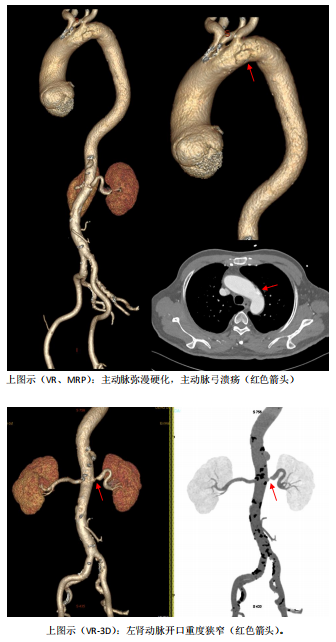

主动脉弓部溃疡及肾动脉狭窄示意图

患者76岁男性,今年3月份以来因心衰气促反复发作,合并上消化道出血等疾病多次入院,临床诊断:巨大主动脉窦瘤合并主动脉瓣重度反流,主动脉弓部溃疡,肾动脉重度狭窄,冠心病,冠脉支架植入术后心功能IV级。考虑患者年龄大合并上消化道出血,病情危重,传统的外科手术基本不可能实施。经导管主动脉瓣置换术(TAVR)是一个比较好的选择,但对于这种巨大主动脉窦瘤合并主动脉瓣重度纯反流,同时合并主动脉弓部溃疡及肾动脉重度狭窄患者,目前并无较好的临床经验借鉴,经查阅文献,国内外未见相同病例经介入手术成功处理的报道。

李存仁主任提出:患者合并主动脉弓部溃疡和肾动脉重度狭窄,TAVR术后可以同时处理主动脉和肾动脉疾病,以降低患者TAVR术后血压升高对主动脉溃疡的影响,建议同时行TEVAR+PYRAS术。